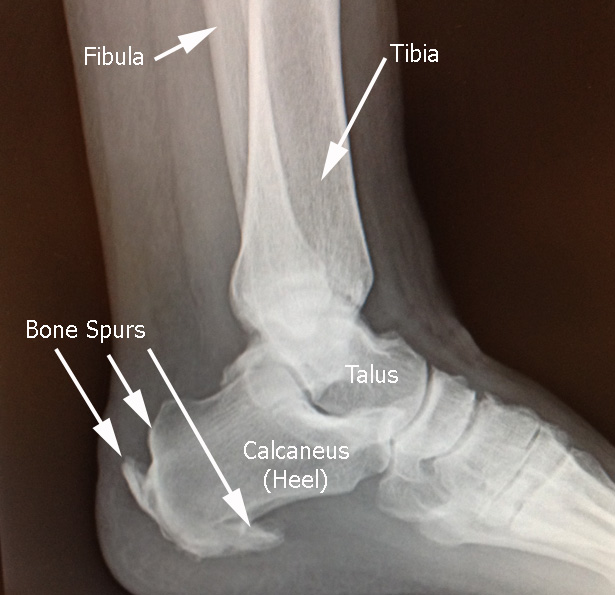

Heel Bone Spur Photograph by Zephyr/science Photo Library

Common Foot Problems | South Coast Foot Surgery

TCM News: TCM Physician Treat Heel Spur Neck Pain with Acupuncture